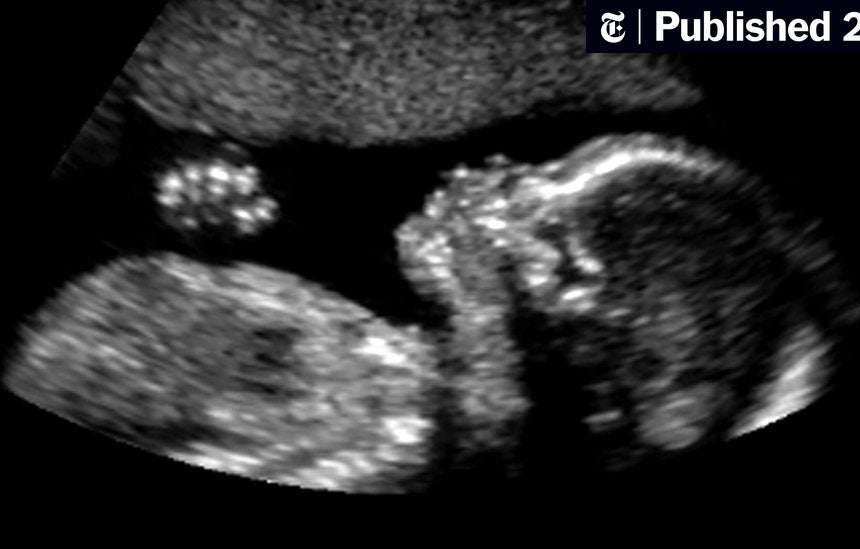

Kriza klimatike po dëmton shëndetin e fetuseve, foshnjave në mbarë botën, kanë zbuluar gjashtë studime të reja.

Shkencëtarët zbuluan se rritja e nxehtësisë lidhej me shtimin e shpejtë të peshës tek foshnjat, gjë që rrit rrezikun e obezitetit në jetën e mëvonshme. Temperaturat më të larta u lidhën gjithashtu me lindjen e parakohshme, e cila mund të ketë efekte shëndetësore gjatë gjithë jetës, dhe me rritjen e shtrimeve në spital të fëmijëve të vegjël.

Studime të tjera zbuluan se ekspozimi ndaj tymit nga zjarret dyfishonte rrezikun e një defekti të rëndë të lindjes, ndërsa ulja e fertilitetit lidhej me ndotjen e ajrit nga djegia e karburanteve fosile, madje edhe në nivele të ulëta. Studimet, të botuara në një botim special të revistës Pediatric and Perinatal Epidemiology, përfshinin globin nga SHBA në Danimarkë, Izrael dhe Australi.

Lidhja midis nxehtësisë dhe shtimit të shpejtë të peshës në vitin e parë të jetës u gjet nga shkencëtarët në Izrael. Ata analizuan 200,000 lindje dhe zbuluan se foshnjat e ekspozuara ndaj temperaturave më të larta 20% të natës kishin një rrezik 5% më të lartë për shtim të shpejtë në peshë.

Një studim në Kaliforni zbuloi se ekspozimi i një nëne ndaj zjarreve në një muaj para mbetjes shtatzënë dyfishoi rrezikun e një defekti të lindjes të quajtur gastroschisis, ku zorrët e foshnjës dhe nganjëherë organe të tjera dalin jashtë trupit përmes një vrime të vogël në lëkurë.

Një e katërta e nënave u ekspozuan ndaj të paktën një dite shumë të nxehtë gjatë shtatzënisë, ditë kur temperatura arrinte 1% të temperaturave historike të verës. Rreziku i çdo lindjeje të parakohshme ishte 15% më i lartë një ditë pas këtyre ditëve shumë të nxehta, zbuluan shkencëtarët. Por rreziku ishte edhe më i lartë për lindjet veçanërisht të hershme, trefishuar për foshnjat e lindura para javës së 28-të dhe ishte gjithashtu më i lartë për 20% të nënave më të pafavorizuara.